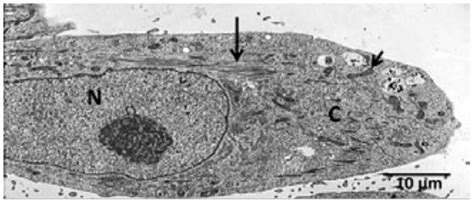

Estas células aplanadas y elongadas se encuentran en la superficie ósea, formando una capa protectora junto con el endostio. Pueden expresar marcadores osteoblásticos y el receptor de la parathormona (PTH). Desempeñan un papel importante en la activación del remodelado óseo.